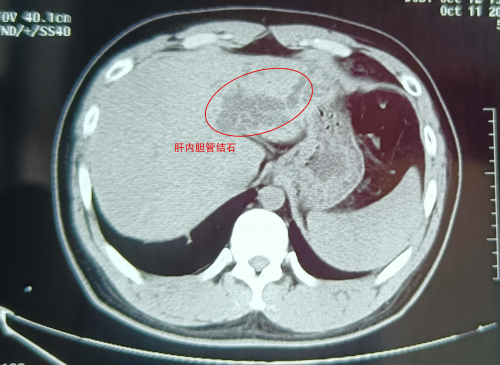

武漢的劉先生怎么也沒(méi)想到,看似普通的腹痛,竟險(xiǎn)些讓自己丟了肝!近日,這位肝膽系統(tǒng)布滿(mǎn)結(jié)石的“小黃人”,緊急求助于武漢京都結(jié)石醫(yī)院。幸運(yùn)的是,因?yàn)槭中g(shù)處理得當(dāng),劉···